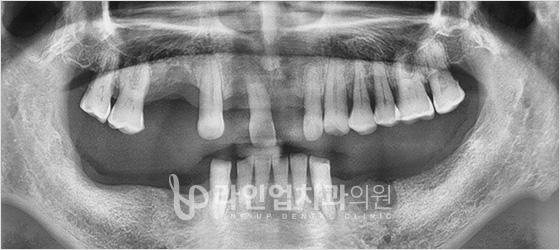

Before

After

Bottom molars implant